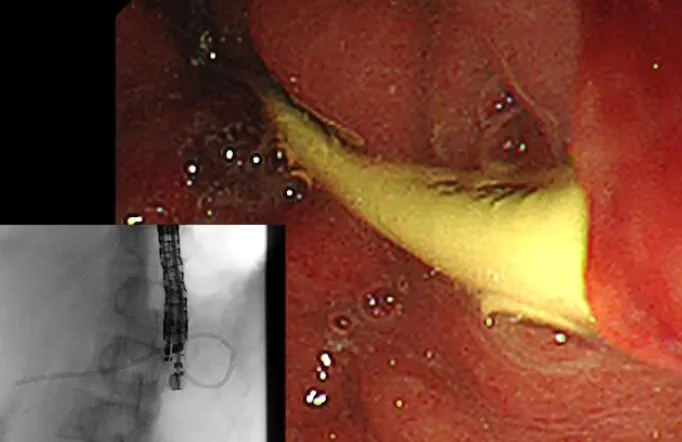

• 閉塞性黄疸に対する超音波内視鏡ガイド下胆道ドレナージ(EUS-BD:EUS-HGS/EUS-CDS)

• 超音波内視鏡ガイド下胆のうドレナージ(EUS-GBD)

• 超音波内視鏡下膵嚢胞ドレナージ(EUS-TD)

• 困難とされているEUS-HGSやEUS-PDも当科では標準化された治療として行っております。